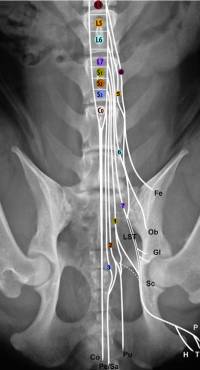

Der Conus medullaris liegt im kaudalen Anteil vom L6 bis zum kranialen Anteil vom L7. Bei kleineren Hunden weiter kaudal. Der Durasack geht bei 80% der Hd bis ins Sakrum. Die Cauda equina entspringt am Conus medullaris und reicht vom L6 bis zum Cd5.